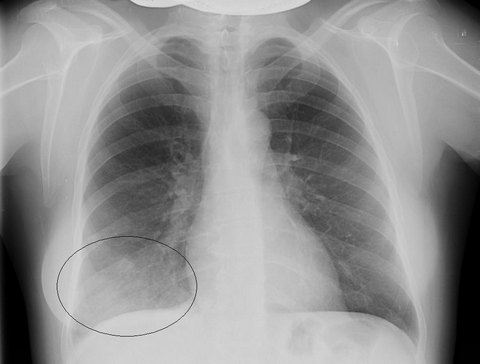

- Рентген. Для того, чтобы определить локализацию очага воспаления проводится рентгенография в прямой и боковой проекциях. На снимке просматривается затемнение пораженного сегмента.

Правосторонняя сегментарная пневмония на рентгенограмме

- рентгенографию грудной клетки;

Рентгенограмма лёгких при сегментарной пневмонии